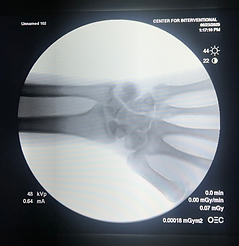

Descriptive: My photograph of my wrist is descriptive because it's sole purpose is to show the bones of my forearm and wrist, enabling the Physician to evaluate the condition of my wrist.